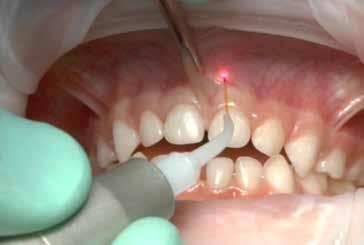

S.V. Paziente di tre anni di sesso maschile, in III Classe scheletrica lieve, con open-bite, deglutizione atipica, contrazione dell’arcata superiore, tendenza alla III Classe. Alla prima visita il paziente presentava un evidente frenulo vestibolare corto, a tetto labiale che, trazionando il labbro superiore, tendeva a ischemizzarsi insieme alla papilla retroincisiva.

In situazioni simili si potrebbe anche attendere ma, poiché si rendeva necessaria una terapia ortodontica, si è proceduto ad eseguire una frenulectomia e il giorno stesso è stato consegnato al paziente l’apparecchio elastodontico per la correzione della malocclusione. Lo scudo vestibolare dell’apparecchio ha contribuito alla guarigione del frenulo stesso determinando una trazione continua sul labbro superiore.

La sequenza terapeutica ha previsto i seguenti step:

• frenulectomia laser;

• terapia elastodontica al fine di ripristinare la corretta crescita scheletrica e dentale.

Fig. 4

Fig. 5 > Immagine intraorale frontale.

Fig. 6 > Immagine intraorale laterale destra.

Fig. 7 > Immagine intraorale laterale sinistra.

Fig. 8 > Dettaglio del frenulo labiale superiore corto.

Figg. 9-11 > Intervento di frenulectomia con laser a diodo.

Figg. 12, 13 > Controllo dopo ventiquattro ore.